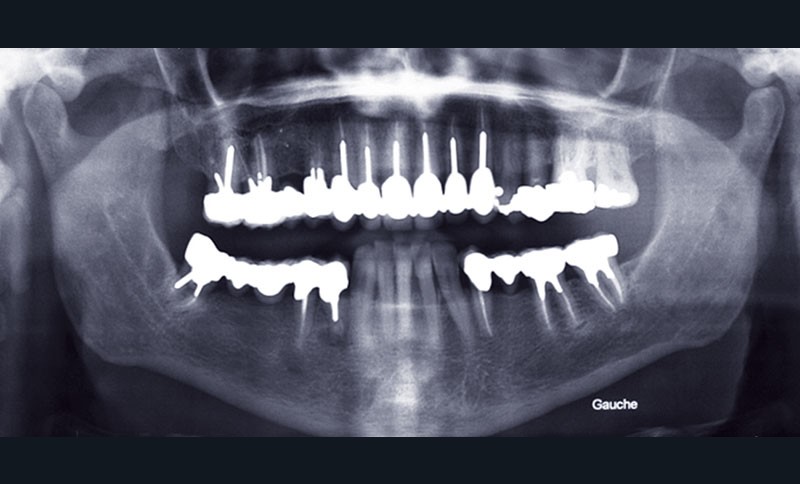

Les possibilités des techniques de collage doivent nous faire passer de concepts biomécaniques à des concepts adhésifs. Le concept suggéré par différents auteurs du « No Post, No Crown » (plus de tenon, plus de couronne) a parfois du mal à trouver une écoute attentive chez certains praticiens pour qui la notion d’acte remboursable reste un facteur majeur décisionnel dans leur thérapeutique. Ce qui peut largement se comprendre dans le système français, mais qui reste préjudiciable pour la pérennité des organes dentaires. Il faut ainsi préciser que Vailati a, dès 2008 [1], mis en avant le problème de la reconstitution d’une dent fortement délabrée dans le cas de reconstruction totale où la préservation tissulaire est le guide thérapeutique majeur. En effet, face à de fortes érosions, la motivation thérapeutique ne devrait plus être de dépulper systématiquement la dent, mettre un ancrage radiculaire métallique et réaliser une coiffe périphérique (fig. 1).